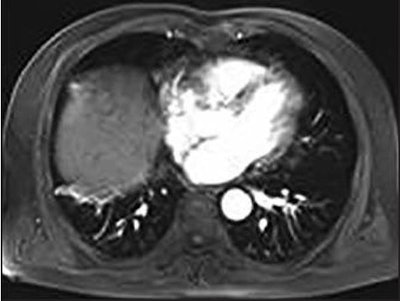

Wang and colleagues enrolled 37 consecutive patients (mean age, 57.2 years) with 37 HCCs located in the hepatic dome who underwent percutaneous cryoablation on a 1-tesla open MRI scanner (Panorama HFO, Philips Healthcare). An MR fluoroscopy T1-weighted gradient field-echo sequence was used to obtain images throughout the procedure, while clinicians employed a freehand technique to confirm the needle's entry and approach to the HCC.

At the six-month follow-up, the researchers saw only one case (3%) of tumor progression, and all 37 patients (100%) were still alive. After one year, they saw two cases (5%) of tumor progression and one death, for a 12-month survival rate of 97%. The death was due to an upper gastrointestinal hemorrhage 10 months after cryoablation.